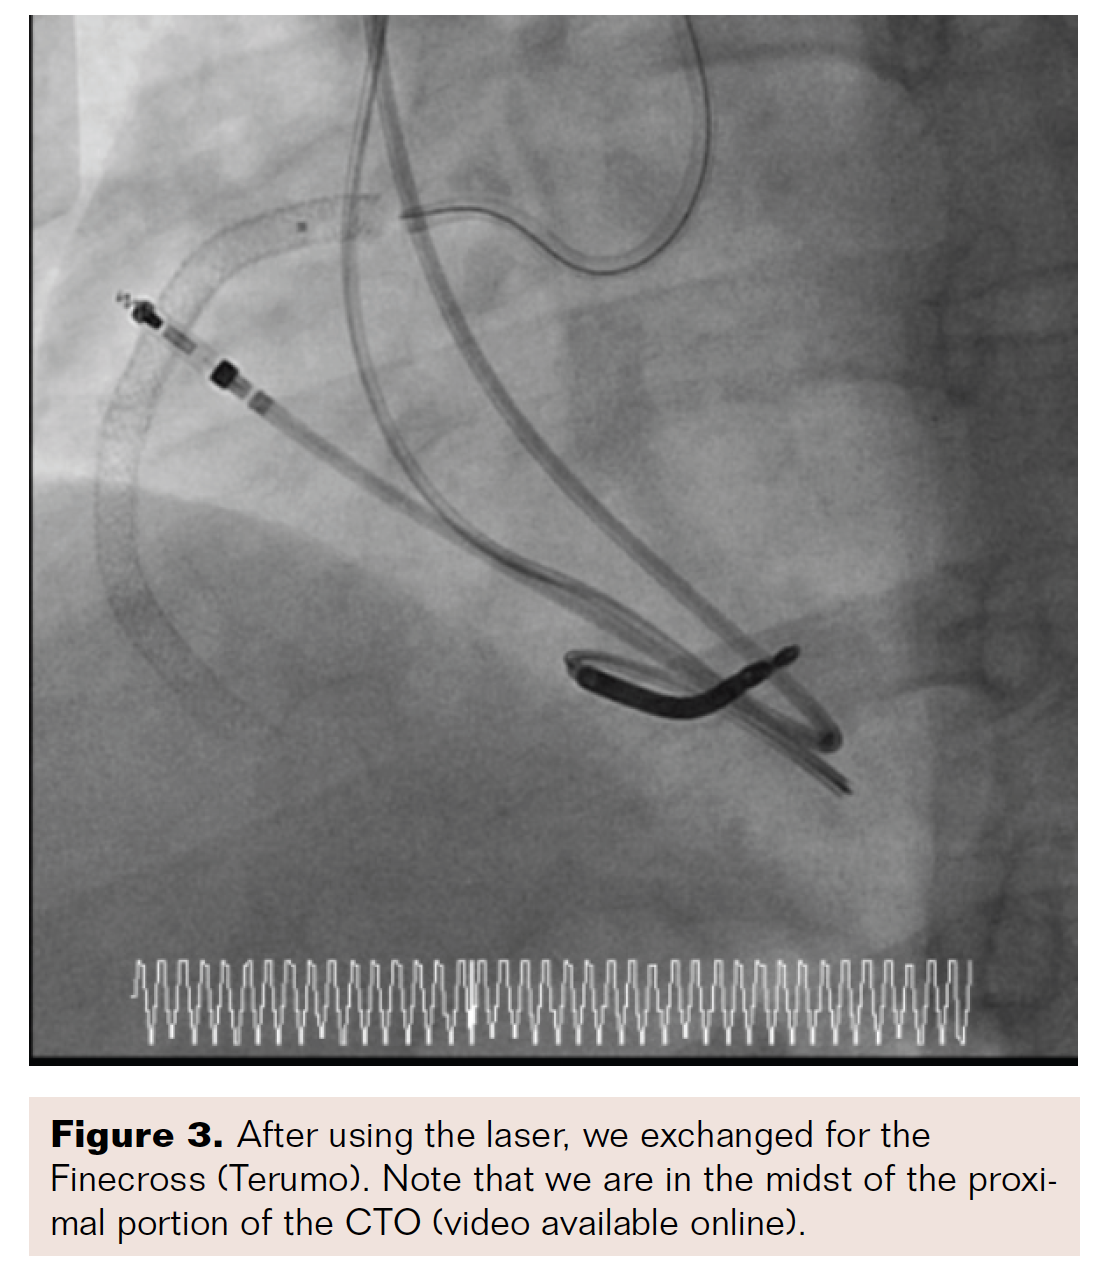

There was an excessive amount of plaque and thrombus in the vessel, so the McNamara catheter (Medtronic) was inserted and 4 mg of intra-arterial tissue plasminogen activator (tPA) was infused in the occluded vessel (Figures 6-8). After re-inserting the .014-inch wire, five slow passes were made with the Indigo CAT RX aspiration catheter in order to remove thrombus from the totally occluded vessel. Afterwards, an angiogram confirmed TIMI-3 flow with no more thrombus observed, but the vessel was diffusely diseased (Figure 9). We performed balloon angioplasty and subsequent stenting, placing a 2.75 × 38 mm Resolute Onyx drug-eluting stent (Medtronic) distally and two 4.5 × 38 mm drug-eluting stents proximally. At the origin of the vessel, a 5 × 20 mm drug-eluting stent was placed using an Ostial Flash balloon (Ostial Corporation) to optimize the origin of this stent (Figure 10). Following this final procedure, angiography demonstrated a widely patent RCA with TIMI-3 flow (Figures 11-12).